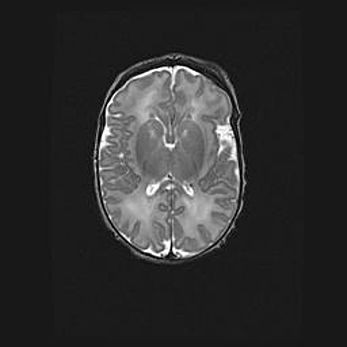

Сообщающаяся гидроцефалия. Кистозная энцефаломаляция головного мозга.

Возраст: 3 месяца 4 дня

Вес: 3100 г

Пол: женский

Окружность головы: 34 см

Срок гестации: 31 неделя

Кистозная энцефаломаляция головного мозга - одна из форм поражения головного мозга в детском возрасте. Характеризуется возникновением множественных и распространённых кист в коре, белом веществе и подкорковых образованиях головного мозга у плодов, новорождённых и детей раннего возраста. Развитие кистозной энцефаломаляции связано с внутриутробной асфиксией и гипотонией, родовой травмой, тромбозом синусов, пороками развития сосудов, инфекциями, сепсисом и другими причинами. Наиболее значимые инфекционные агенты: вирусы простого герпеса, цитомегалии, краснухи, токсоплазмы, энтеробактерии, золотистый стафилококк и другие.